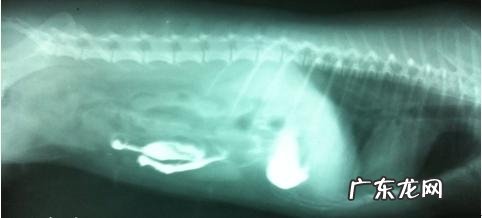

x光图

灌服钡餐半小时后,钡餐关键在胃内 。孕妇左侧睡

灌服钡餐九十分钟后,钡餐仍在胃内,向胃的幽门方位流去,孕妇左侧睡